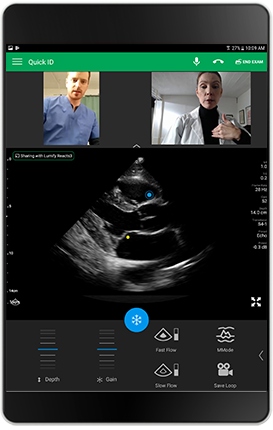

Live integrated tele-ultrasound

Real-time collaboration can make a difference for some patients – when making rounds, in your clinic, or at a community scanning event. Lumify with Reacts capability allows you to simultaneously stream live ultrasound images, video and audio, providing the critical, real-time information you are seeing with other experts, and get their feedback in real time. It’s collaboration that can make a real difference in patient care.